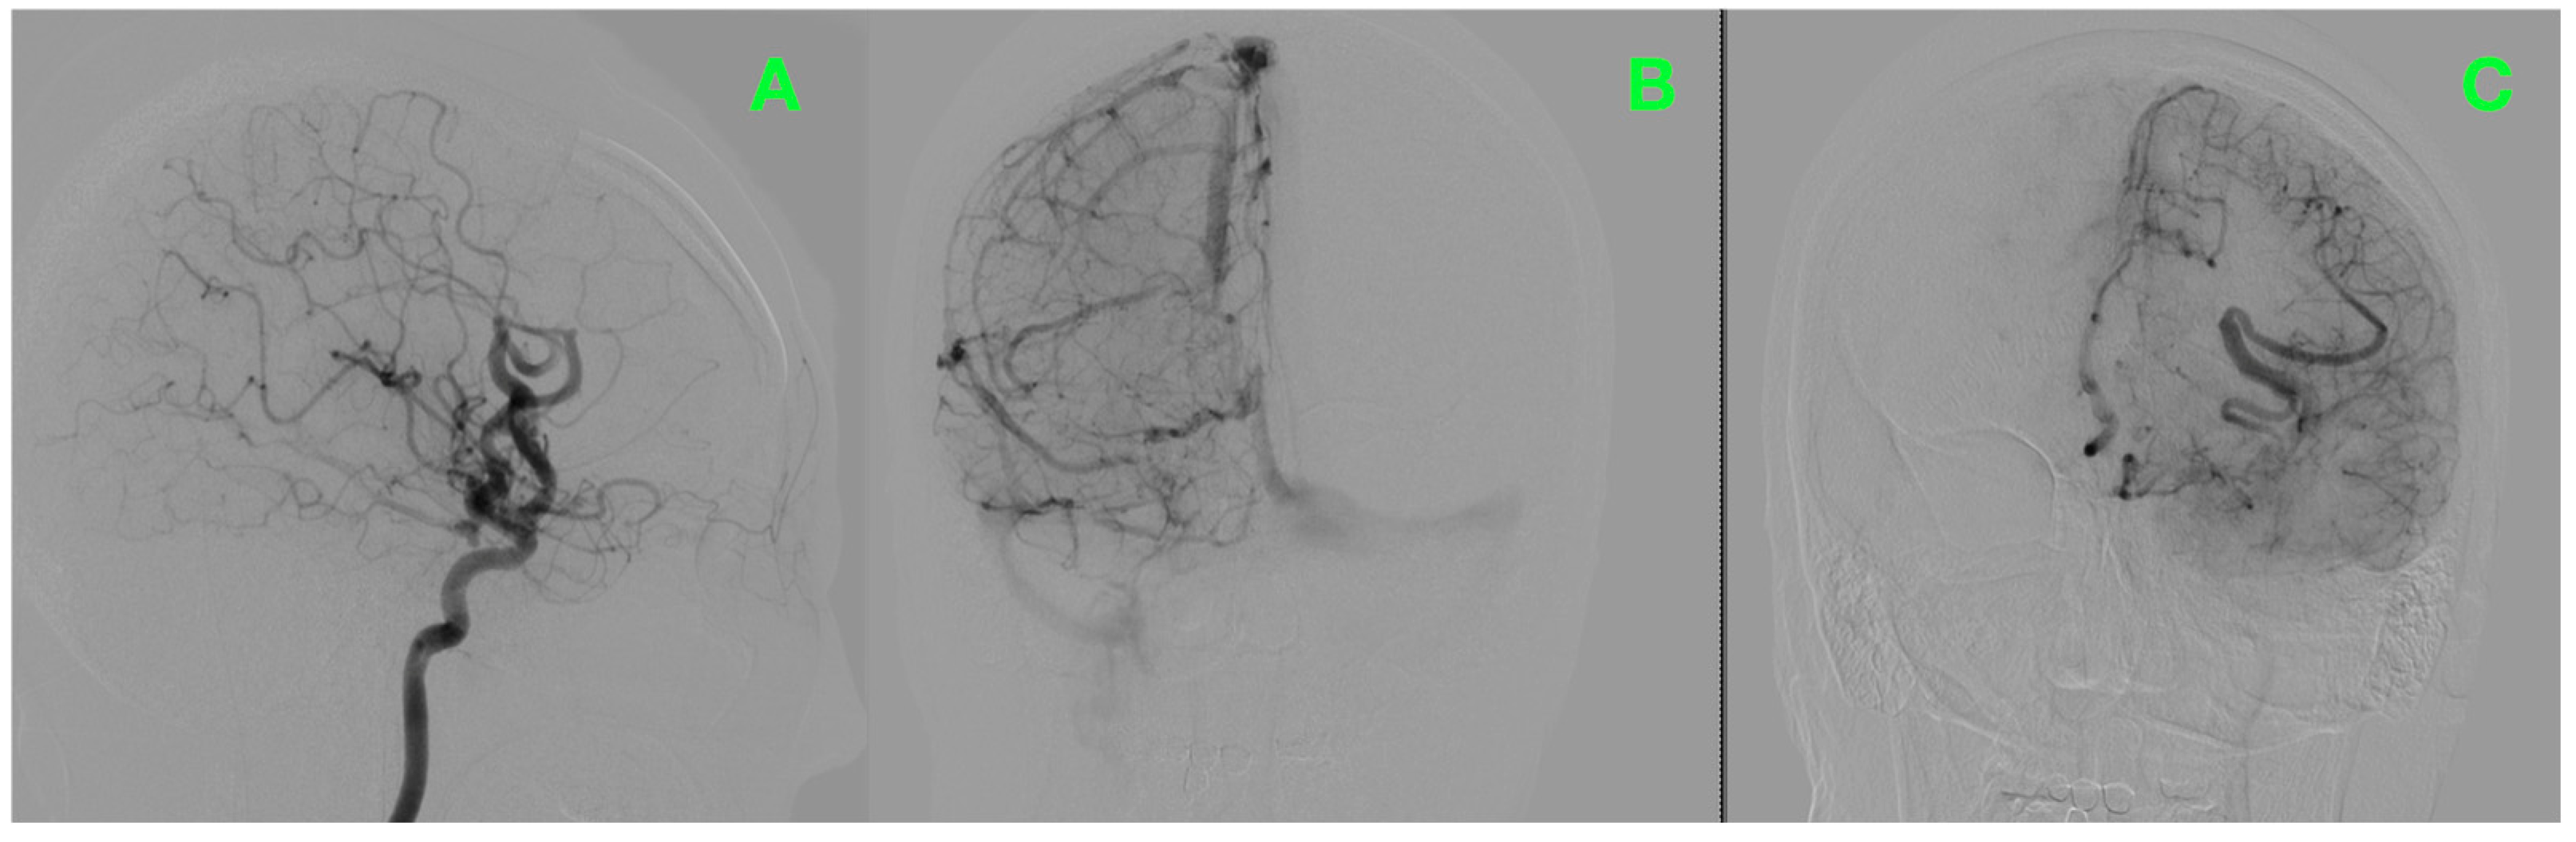

2.4. Surgical Intervention

2.5. Postoperative Course

2.6. Initial Imaging and Clinical Monitoring